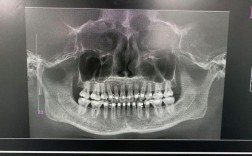

全面评估:制定“一人一案”的治疗计划

正畸治疗前,医生需通过口腔检查、X光片(曲面断层片、头颅侧位片)、CBCT(三维影像)、牙齿模型等,全面评估患者的牙齿情况(龋齿、牙周健康)、牙根形态、牙槽骨密度、颌骨关系(骨性错颌还是牙性错颌)、面部软组织轮廓等,骨性“地包天”可能需要配合正颌手术,单纯矫正无法解决问题;而牙周炎患者需先治疗牙周病,否则矫正会加重病情,这些评估是个人无法完成的,也是避免风险的前提。